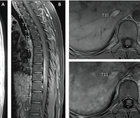

Case Report: Longitudinally Extensive Transverse Myelitis

Ylec Mariana Cardenas, MD; Lakshmi Leishangthem, MDYlec Mariana Cardenas, MD; Lakshmi Leishangthem, MD - Stroke